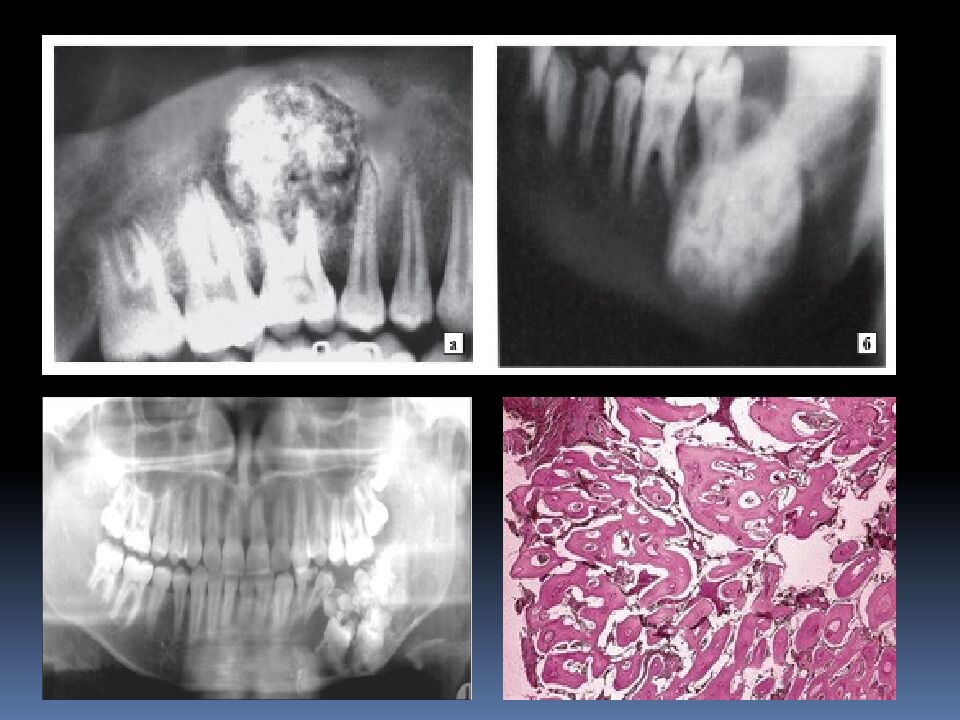

• Одонтома

Доброкачественная одонтогенная опухоль, состоящая из различных зубных тканей, это порок развития зубных тканей. Одонтомы бывают составные и сложные.